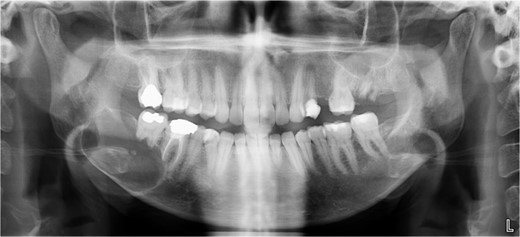

A 40-year-old woman presented with swelling on the right side of her mandible. She had completed orthodontic treatment 2 years earlier. A panoramic radiograph showed a unilocular radiolucency extending from the mandibular angle to the right first molar region (Figs 1–3).

Panoramic radiograph showing a unilocular radiolucency extending from the right mandibular angle to the right first molar region.

Panoramic radiograph highlighting the extent of the lesion from the mandibular angle to tooth #46.